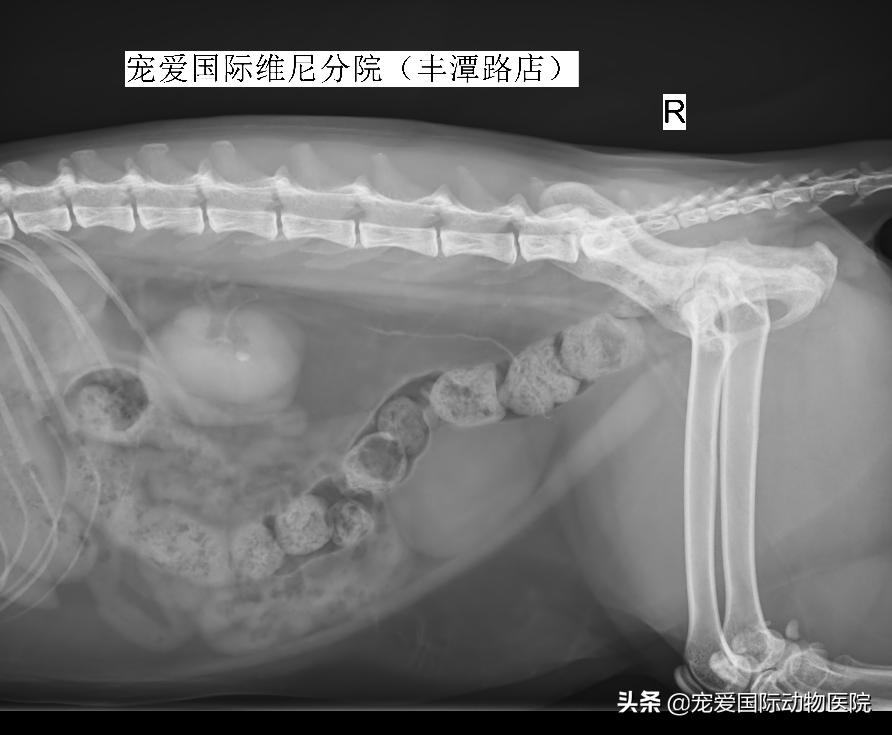

B超检测,见右侧肾盂扩张

内有一直径6MM结石

右侧肾结石,右侧输尿管堵塞

部分患宠肾结石可能会在数小时或数日自行排出,反复进行X光片检查可帮助追踪其过程。若结石引起输尿管阻塞、肾衰竭,或者结石造成输尿管严重损伤等,通常需借助外科手术手段,但因为猫的输尿管特别细,输尿管结石取出手术还需要特殊的放大设备等。

↑膀胱结石,肾结石,肾衰,肝功异常的小黄,血尿严重,体温36℃,寒颤发抖明显,无食欲,严重脱水,三天的治疗体温37.5,食欲正常,精神状态正常,后天复查,但是其实这些只是指标未治本。

↑猫咪突发尿闭,检查发现不仅有肾结石和膀胱结石,还有严重的肥厚性心肌病。通过治疗,出院定期复查保障身体健康。